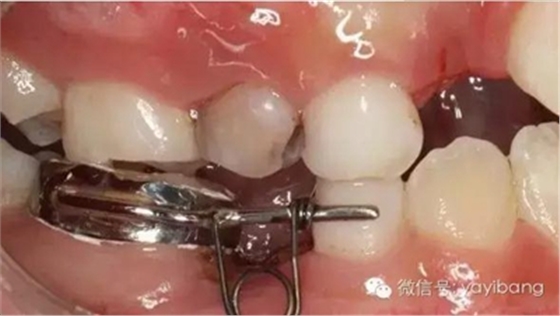

42、牙面拋光,試合制作好的間隙恢復(fù)器,將曲簧水平部分形成與牙面弧形一致,羧酸鋅水門汀粘結(jié)固定

43、粘結(jié)后的頰面觀